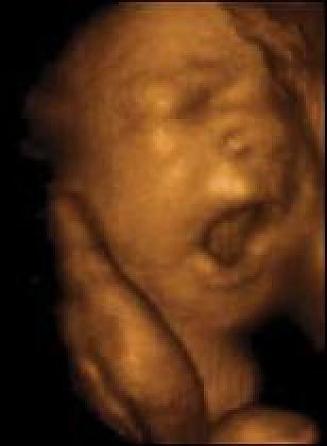

Pentru că filmul lui Nathanson ne arată că avortul nu este eliminarea unui conglomerat de „țesuturi” sau „înlăturarea unui nedorit produs al concepției” – de parcă am vorbi în termeni de economie politică despre realitatea cea mai intimă a persoanei umane. Nu! Avortul este ceea ce a înfățișat, începând cu Nathanson, mișcarea Pro-Viață: este crimă. Înseamnă ruperea în bucăți a unui prunc în pântecele mamei lui, zdrobirea lui pe bucăți și eliminarea lui. Este o crimă împotriva celei mai fragile persoane, celei mai lipsite de apărare. Cum s-a ajuns acolo?

[1] „Strigătul mut” („The Silent Scream”) este un documentar care arată că avortul nu „îndepărtează un ghem de ţesuturi”, aşa cum afirmă susţinătorii acestuia, ci ucide o ființă vie. Filmul prezintă şi explică înregistrarea cu ultrasunete a unui avort prin aspiraţie, în primul trimestru de sarcină. Imaginea copilului nenăscut, ferindu-se de chiuretă şi căscând gura într-un „strigăt mut” în încercarea de a scăpa de instrumentul ucigaş, este una din cele mai dramatice scene captate vreodată. Filmul este realizat şi prezentat de dr. Bernard Nathanson, pe care „Strigătul mut” l-a schimbat total. Din director al uneia din cele mai mari clinici de avorturi din New York şi fondator al organizaţiei care a legalizat avortul în SUA (NARAL), dr. Nathanson a devenit un mare luptător pentru cauza vieţii. Acest film nu are nimic a face cu religia. Dr. Nathanson s-a declarat ateu. Nu are nimic a face cu „convingerile personale”. Este doar crudul adevăr: avortul nu înseamnă „dreptul femeii de a alege”, ci o crimă comisă „legal” împotriva unei fiinţe umane.